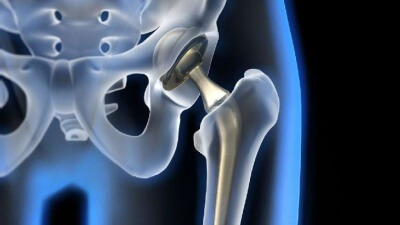

Эндопротезы тазобедреного сустава

Костная пластика при эндопротезировании тазобедренного сустава

Опыт применения остеопластических материалов при ревизионном эндопротезировании тазобедренного сустава